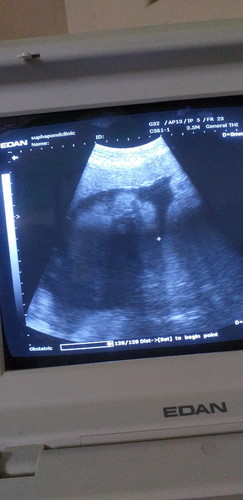

33 วีค

ตอนนี้ท้อง 33 วีค นน.น้องอยู่ที่ 2080 แต่ยังไม่กลับหัวอยากรุ้น้องจะกลับหัวตอนไหนกลัวโดนผ่า